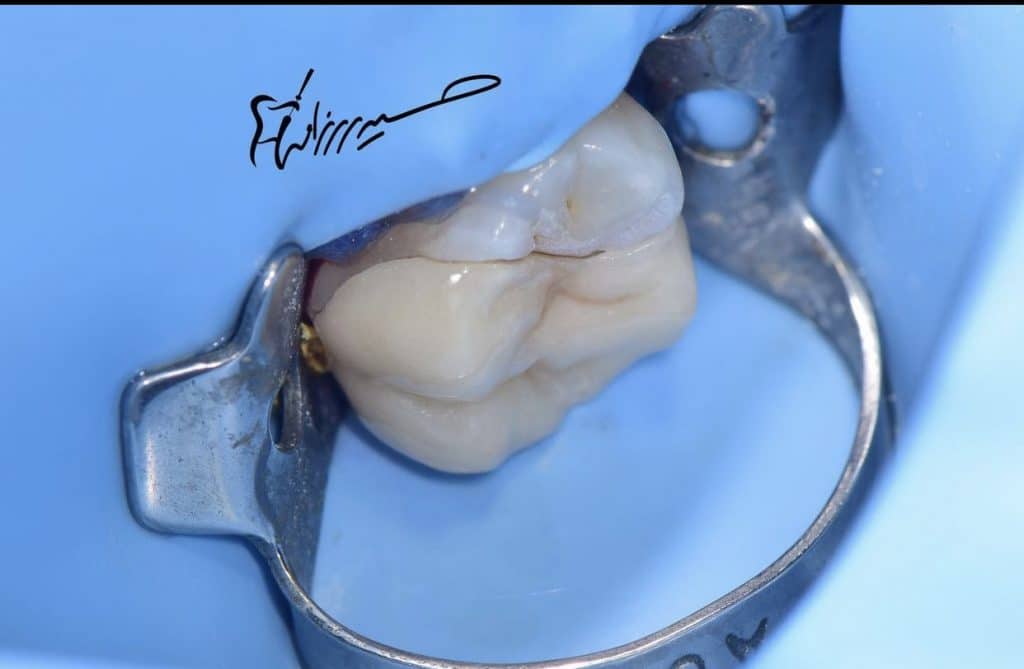

Endocrown(overlay!) prep

Cementation done with heated Apx composite from kurary .

Prep and isolation

Check the restoration

Immediate after cementation